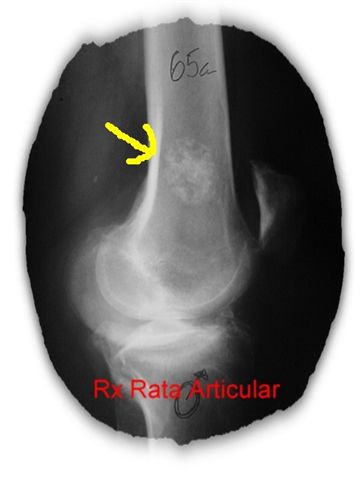

RATA ARTICULAR